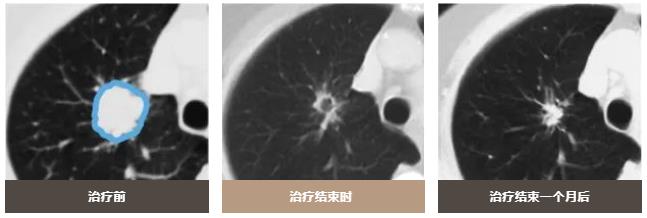

治療效果

質子治療可以減少對周圍正常肺組織的照射劑量,只對病變部位進行集中照射。

在開發各種新型抗癌藥物和分子靶向藥物的同時,人們也在嘗試通過增加放射劑量來提高治療的效果。雖然增加放射劑量對周圍正常肺部的影響令人擔憂,但質子療法有可能在不增加副作用的情況下增加照射劑量。今后,人們還會利用質子療法進行放射治療劑量增加試驗,以便在確認安全性的同時提高治療效果。